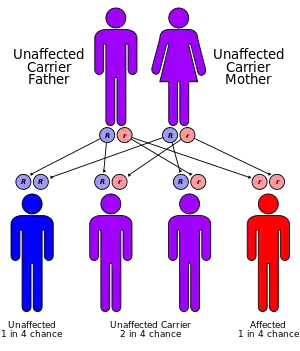

Two forms of the disorder exist, dominant and recessive, of which the former is more common. Patients with the dominant version often suffer moderately from the aforementioned symptoms. Recessive cases, on the other hand, are usually more physically marked, and individuals may exhibit more skeletal abnormalities.[2] The recessive form is particularly frequent in Turkey.[3] However, this can likely be explained by a common ancestor, as these patients' families can be traced to a single town in Eastern Turkey.[4] Clusters of the autosomal recessive form have also been documented in Oman and Czechoslovakia.[1]

Genetics

Genetic studies have linked the autosomal recessive form of the disorder to the ROR2 gene on position 9 of the long arm of chromosome 9.[1] The gene is responsible for aspects of bone and cartilage growth. This same gene is involved in causing autosomal dominant brachydactyly B.[1]

The autosomal dominant form has been linked to three genes – WNT5A, Segment polarity protein dishevelled homolog DVL-1 (DVL1) and Segment polarity protein dishevelled homolog DVL-3 (DVL3). This form is often caused by new mutations and is generally less severe than the recessive form. Two further genes have been linked to this disorder – Frizzled-2 (FZD2) and Nucleoredoxin (NXN gene).[10] All of these genes belong to the same metabolic pathway – the WNT system. This system is involved in secretion for various compounds both in the fetus and in the adult.

A fetal ultrasound can offer prenatal diagnosis 19 weeks into pregnancy. However, the characteristics of a fetus suffering from the milder dominant form may not always be easy to differentiate from a more serious recessive case. Genetic counseling is an option given the availability of a family history.[1]